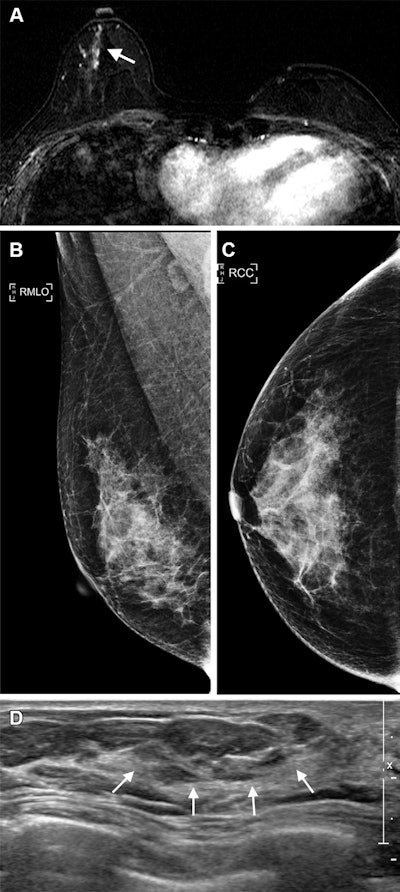

Images in a 40-year-old woman who underwent breast-conserving surgery for left breast cancer and a surveillance breast MRI examination 25 months after surgery. (A) Axial T1-weighted contrast-enhanced subtraction MRI scan shows a newly developed nonmass enhancement (arrow) in the right central breast. (B) The right mediolateral oblique (RMLO) and (C) right craniocaudal (RCC) mammograms, obtained on the same day, show heterogeneously dense breast tissue that was assessed as being negative for cancer. (D) MRI-directed US image in the radial plane shows a corresponding 14-mm nonmass lesion (arrows) in the right lower outer breast, which was confirmed estrogen receptor-positive, progesterone receptor–positive, and human epidermal growth factor receptor 2-negative T1N0 mucinous carcinoma. Image and caption courtesy of the RSNA.